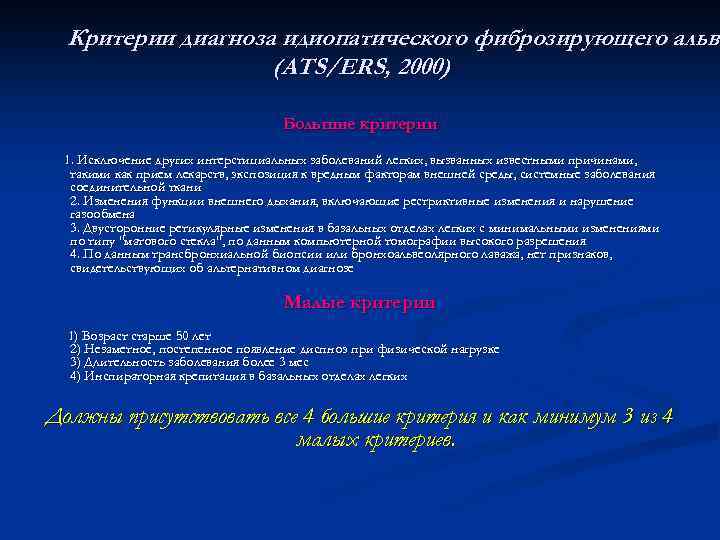

Критерии диагноза идиопатического фиброзирующего альве альв (ATS/ERS, 2000) Большие критерии 1. Исключение других интерстициальных заболеваний легких, вызванных известными причинами, такими как прием лекарств, экспозиция к вредным факторам внешней среды, системные заболевания соединительной ткани 2. Изменения функции внешнего дыхания, включающие рестриктивные изменения и нарушение газообмена 3. Двусторонние ретикулярные изменения в базальных отделах легких с минимальными изменениями по типу "матового стекла", по данным компьютерной томографии высокого разрешения 4. По данным трансбронхиальной биопсии или бронхоальвеолярного лаважа, нет признаков, свидетельствующих об альтернативном диагнозе Малые критерии 1) Возраст старше 50 лет 2) Незаметное, постепенное появление диспноэ при физической нагрузке 3) Длительность заболевания более 3 мес 4) Инспираторная крепитация в базальных отделах легких Должны присутствовать все 4 большие критерия и как минимум 3 из 4 малых критериев.